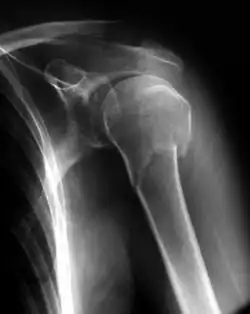

Fratura óssea é uma situação em que há perda da continuidade óssea, com a separação de um osso em dois ou mais fragmentos após um traumatismo.

Nas fraturas simples não há perfuração da pele, ao contrário do que acontece nas fraturas expostas, onde pode ocorrer uma infecção bacteriana, havendo por vezes a necessidade de suturar a ferida.